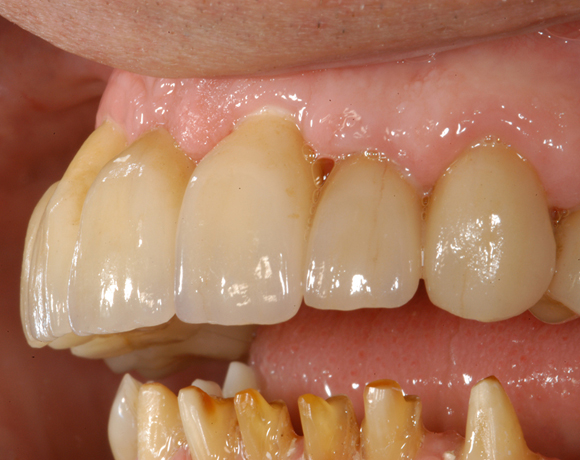

6 Implantate und viele Kronen und Brücken

Mit dem zweiteiligen vollkeramischen Implantat lassen sich auch große Lücken überbrücken.

Im vorliegenden Patientenfall waren die Zähne 11 – 26 mit einer provisorischen Brücke versorgt, der Patient konnte damit aber nicht essen. Auch im Unterkiefer waren die vorhandenen Kronen und Brücken insuffizient. Es wurde eine komplette Neuversorgung für Ober- wie Unterkiefer geplant.